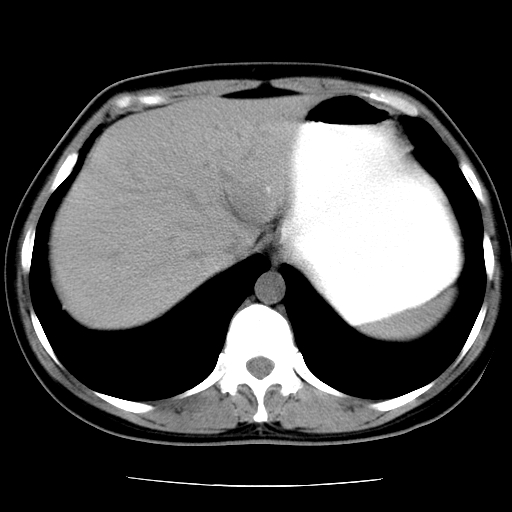

标题: CT16892:女40Y,急性阑尾住院!

女40y,急性阑尾住院!术前发现请会诊!

考虑门静脉瘤样扩张可能,建议增强扫描

胰头假性囊肿也有可能,建议增强

病灶位于门静脉的位置 ,有层面显示血管夹层样改变 ,考虑是门静脉瘤样病变1

病灶位于门静脉的位置 ,有层面显示血管夹层样改变 ,考虑是门静脉瘤样病变,建议进一步增强ct检查。

肝胃间隙良性占位病变,考虑囊肿可能性,不除外神经源性肿瘤,建议增强

肝门区囊性占位,壁有钙化,考虑良性。来源难定。